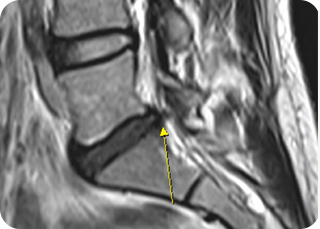

신경성형술(PEN) 사진1

신경성형술(PEN) 사진2

2

신경성형술(PEN)

가느다란 특수 카테터를 삽입해 유착된 신경을 풀어주고 약물을 주입하는 방식입니다.

절개 없이 진행되며, 만성 통증 환자에게 효과적입니다.

• #척추·관절 고주파 열치료

• #수핵성형술

• #섬유륜성형술

풍선확장술 사진1

풍선확장술 사진2

3

풍선확장술

미세한 풍선을 신경관이나 협착 부위에 삽입해 좁아진 공간을 확장시킨 뒤

약물을 투여합니다. 신경 압박을 줄이고 혈류를 개선하여 통증 완화와

기능 회복에 도움을 줍니다.

• #척추관협착증

• #허리디스크(추간판 탈출증)

• #수술 후 통증 증후군 등